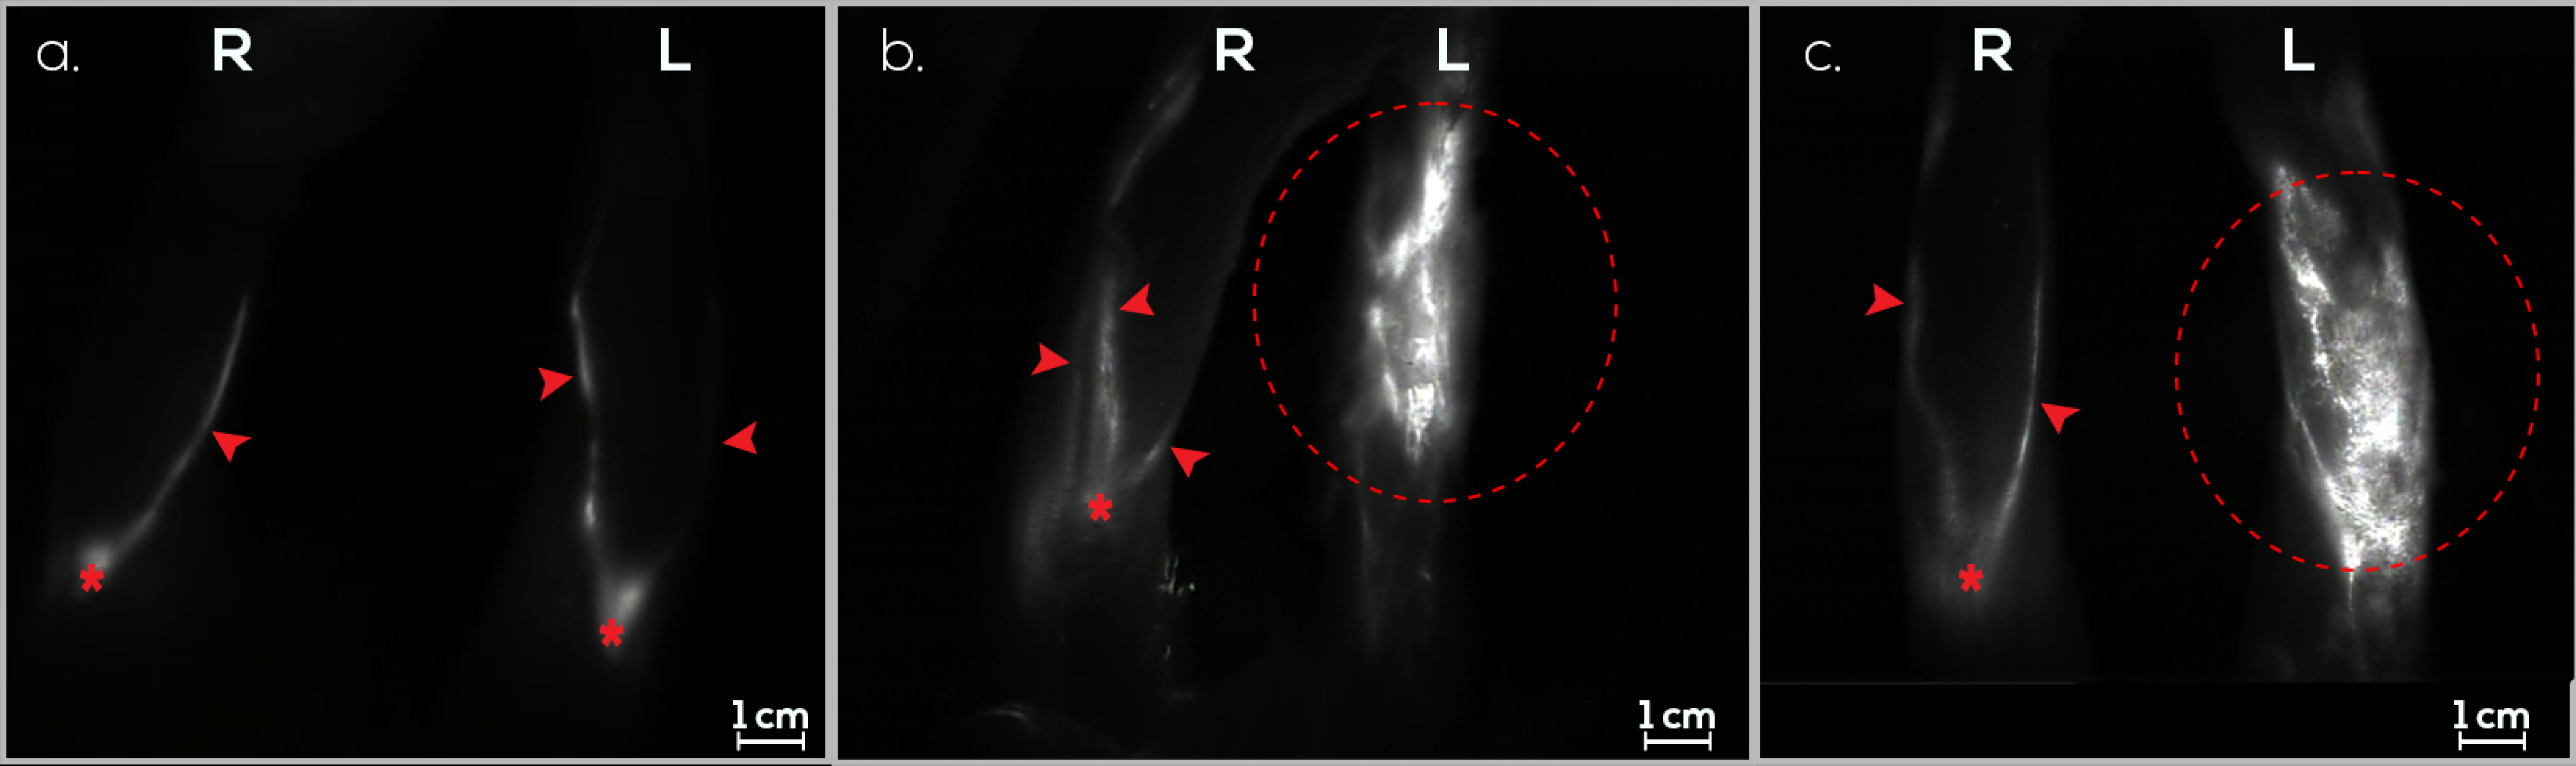

3.1. Treatment Group (G1)

3.2. Preventive Group (G2)

3.3. Control Group (G3)

3.4. Follow-Up Assessments